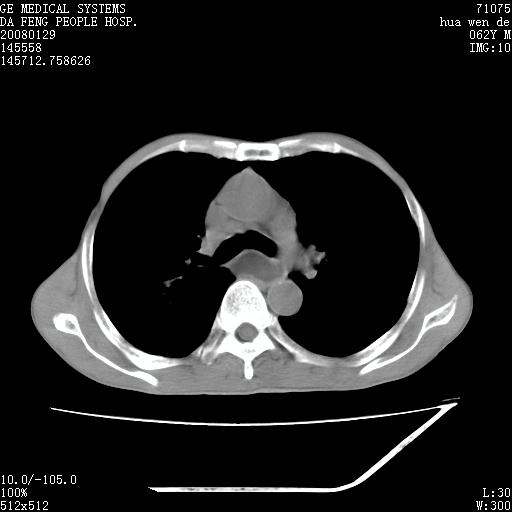

男性,67岁。作肺部检查时发现

考虑:胸腔胃并支气管瘘(并发肺炎,肺脓肿形成)。

理由:1、右上肺内病灶,空洞形成,有液平。

2、肺内多处炎症。

考虑:胸腔胃并支气管瘘(并发吸入肺炎,肺脓肿形成)。

3、前段肺内炎症,支气管引流通畅,与肿块无关系。

1.整个食管扩张,未见明显占位性病变,贲门区亦未见明显占位病变,考虑:贲门失驰缓症;

2.右上肺病变边缘可见毛刺,囊壁厚度不均匀,周围境界较清楚,未见炎性渗出性影,右上肺外带可见片状影,边缘不清,考虑:肺癌伴空洞形成、右上肺炎。

食管全程扩张,壁均匀不厚,喷门失弛缓症

右上肺空洞可见液平,临近肺野磨玻璃密度,考虑1.结核2.脓肿